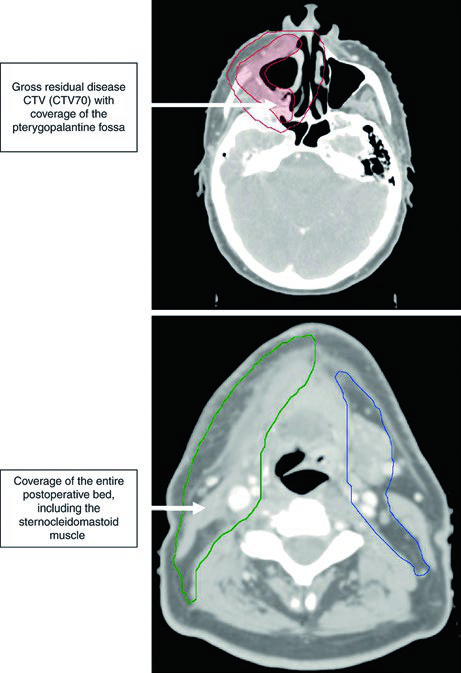

Caso Clínico: Trígono Retromolar T4aN2b

La Figura 6.3 demuestra un CEC de trígono retromolar, T4aN2b, con compromiso del pterigoideo medial, post-resección con enfermedad residual macroscópica y vaciamiento cervical derecho. El CTV70 (rojo sombreado) se delinea basándose en los hallazgos operatorios y las imágenes pre y postoperatorias.

El CTV59,4 se muestra en rojo (región tumoral) y verde (cuello ipsilateral). El CTV54 (azul) incluye los niveles IB a IV contralaterales.

La fosa pterigopalatina funciona como puerta de entrada para la diseminación tumoral hacia la fosa craneal media. Su cobertura adecuada es esencial cuando existe invasión del músculo pterigoideo. Los volúmenes postoperatorios deben incluir todo el lecho quirúrgico, utilizando la inflamación y edema tisular en la TC de planificación para delimitar las áreas de manipulación quirúrgica.